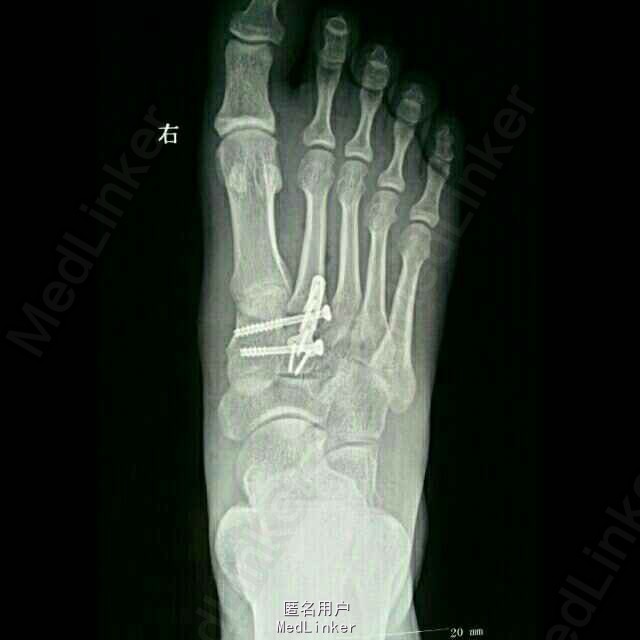

诊断:1.右足第2、3跖骨基底部骨折(Lisfranc损失) 2.右足内侧楔骨骨折 3.骰骨骨折 治疗:切开复位内固定

本例Lisfranc损伤涉及内侧柱和中间柱,中足稳定性破坏,足弓增宽,保守治疗效果很差,需采取内固定方法治疗。